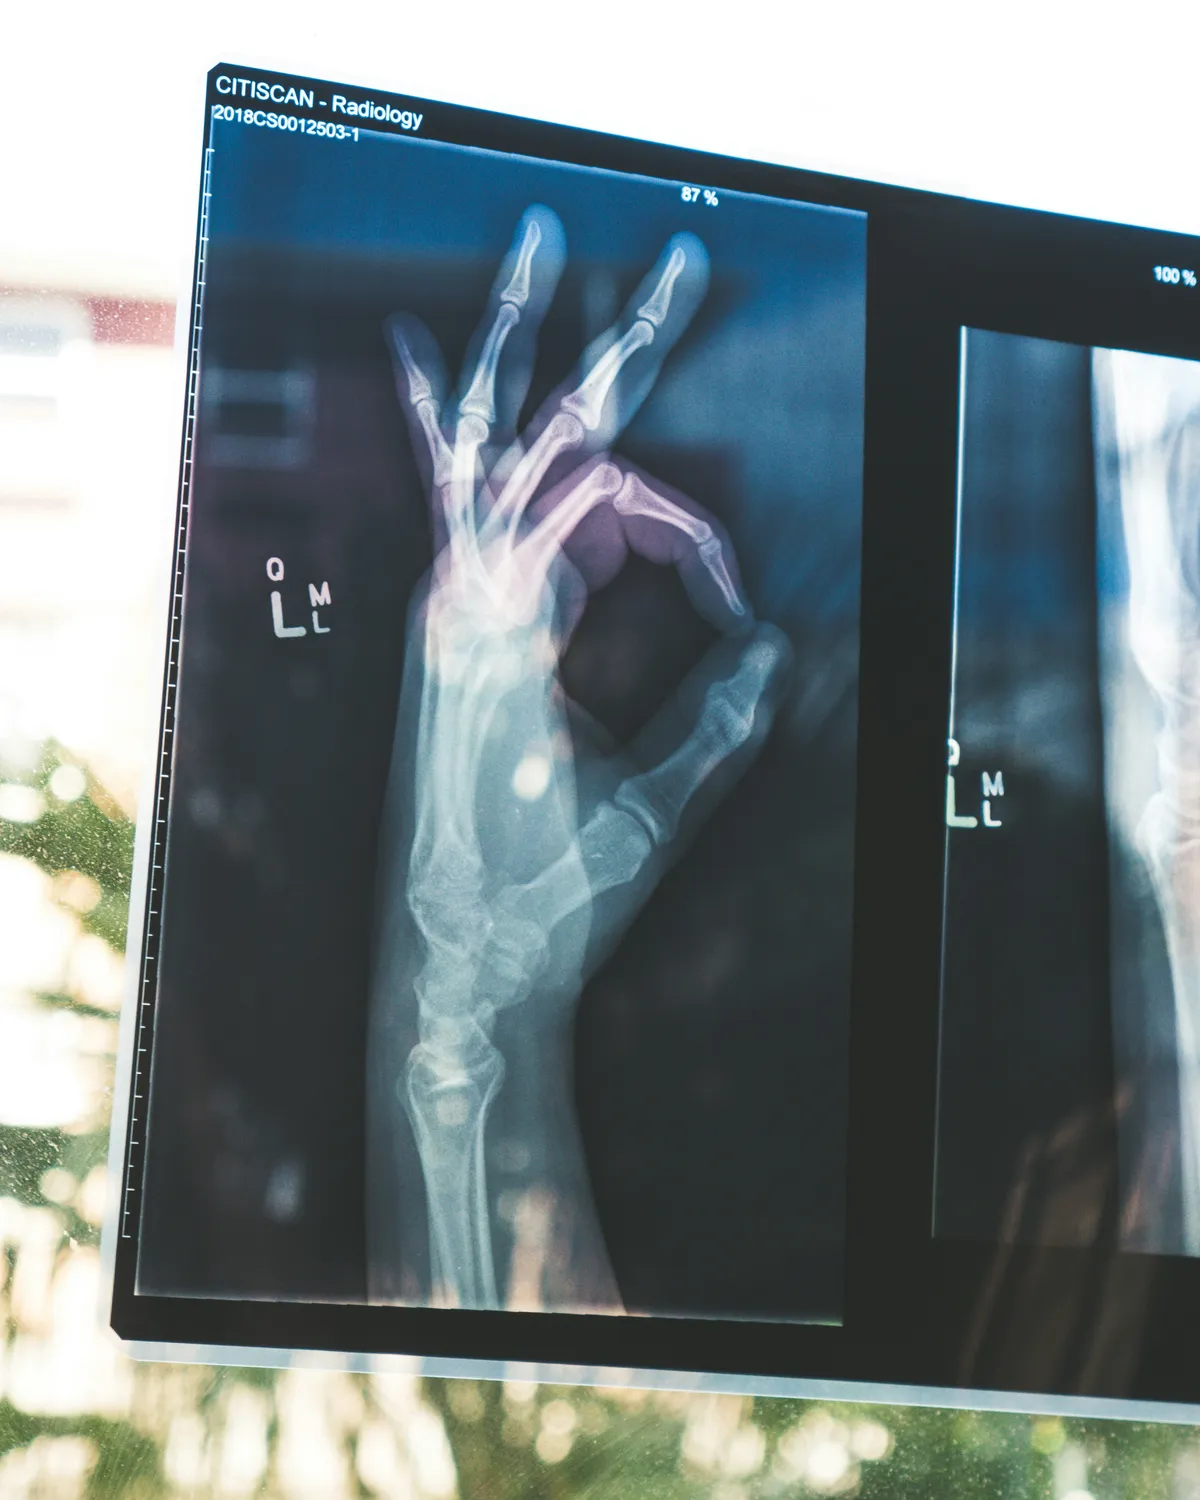

Our Orthopaedics and Trauma department offers expert evaluation and treatment for fractures, joint conditions, sports injuries, and musculoskeletal disorders. With skilled specialists and modern diagnostic support, we deliver safe and effective care for patients of all ages.

Immediate and precise care for injuries and accidents.